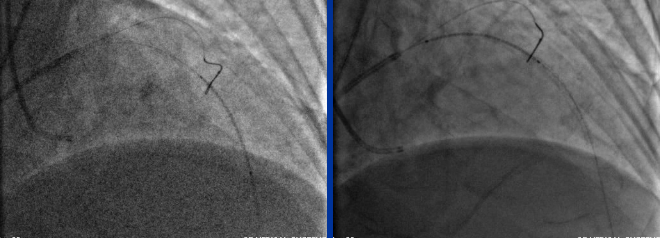

CAG (2016-1-4)

RCA-PCI

LCX-PCI (2016-1-7)

RE-CAG: (2016-2-10)

入路:右桡 6F JR4.0 右股7F EBU3.75

Fielder XT Finecross LEGEND 1.25*15mm

VOYAGER 2.5*15mm、Excel 2.5*36mm、Excel 2.75*36mm

术后

识别心力衰竭的病因(包括诱因)是我们治疗的基础。通过临床分析,我们认为该患者为缺血诱发的心力衰竭,所以在纠正心功能不全时并未停用倍他乐克缓释片,并在积极抗缺血药物治疗的基础上,尽早全面评估手术的风险及获益,经过充分准备,顺利完成PCI手术,开通血管改善缺血。